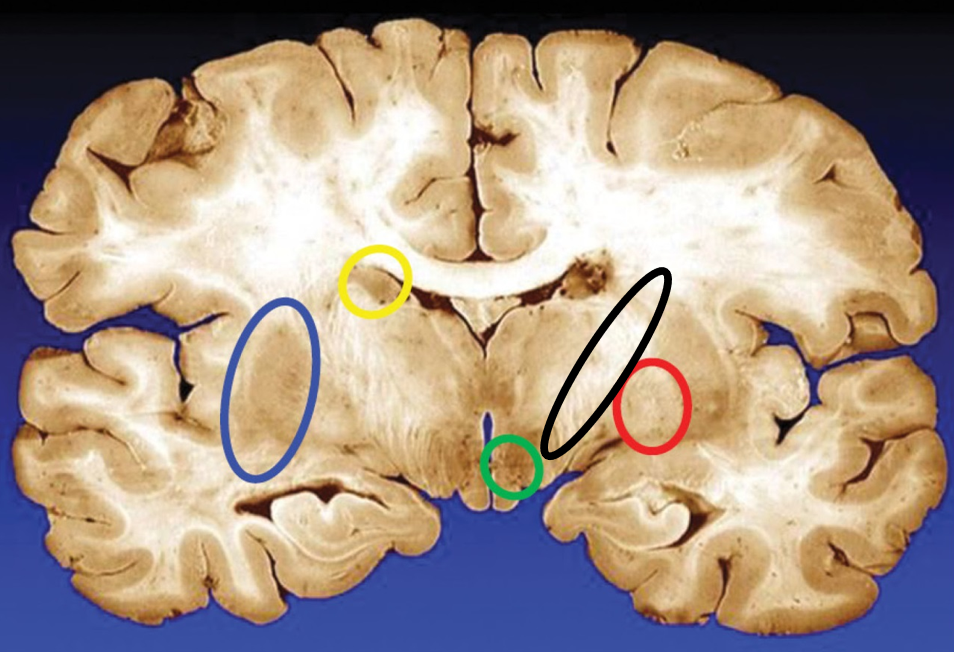

blue

putamen

yellow

caudate

green

subthalamic nuclei

black

internal capsule

red

globus pallidus

name the condition

Huntington’s (reduced caudate)